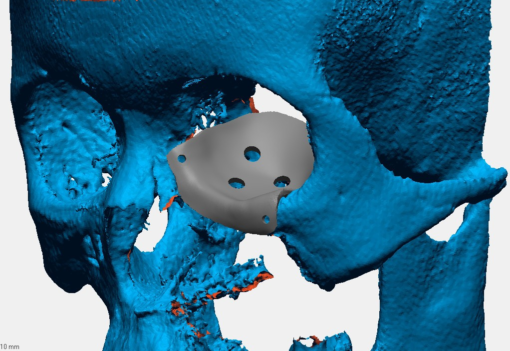

Mảnh ghép tạo hình hốc mắt

Mảnh ghép tạo hình hốc mắt

Vật liệu: vật liệu y sinh PEEK

Công nghệ: công nghệ in 3D

Thuộc đề tài/dự án nghiên cứu: Là sản phẩm của đề tài KHCN cấp TP. Hà Nội

Danh mục: Dạng chấn thương chỉnh hình

Mảnh ghép tạo hình hốc mắt

Vật liệu: vật liệu y sinh PEEK

Công nghệ: công nghệ in 3D

Thuộc đề tài/dự án nghiên cứu: Là sản phẩm của đề tài KHCN cấp TP. Hà Nội